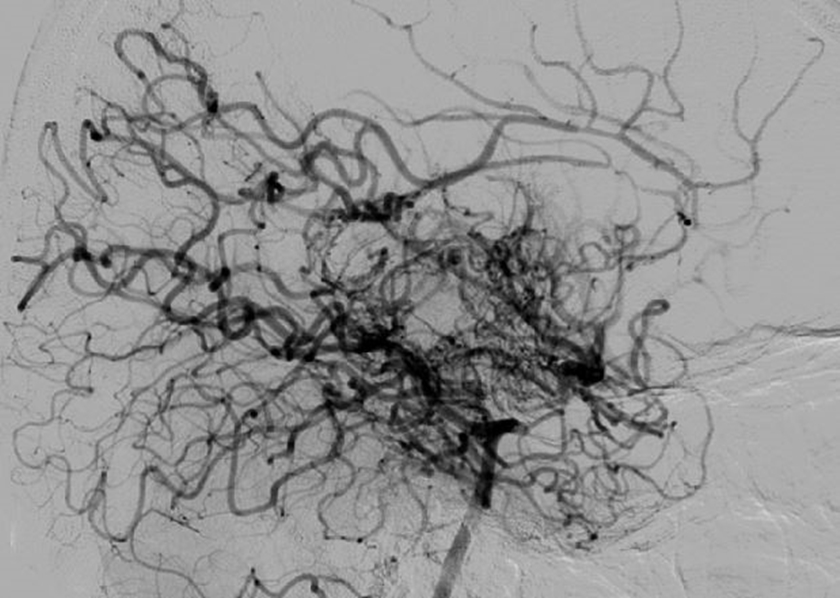

모야모야병은 뇌질환입니다. 뇌혈관이 좁아지거나 막히게 되어서 허혈이 진행하게 되면 뇌기저부에 이상혈관이 만들어 지게 되는데 이상혈관의 모양이 연기가 피어오르는 모양처럼 보인다고 합니다.